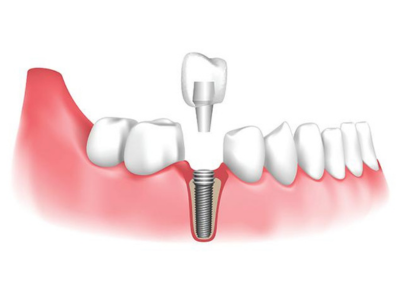

Dental Implant

Dental implant surgery is a procedure that replaces tooth roots with metal, screw like posts and replaces damaged or missing teeth with artificial teeth that look and function much like real ones.

Dental implant surgery can offer a welcome alternative to dentures or bridgework that doesn & fit well and can offer an option when a lack of natural teeth roots doesn’t allow building denture or bridgework tooth replacements.

Dental Implant

Dental implant surgery is a procedure that replaces tooth roots with metal, screw like posts and replaces damaged or missing teeth with artificial teeth that look and function much like real ones.

Dental implant surgery can offer a welcome alternative to dentures or bridgework that doesn & fit well and can offer an option when a lack of natural teeth roots doesn’t allow building denture or bridgework tooth replacements.

In most cases, anyone healthy enough to undergo a routine dental extraction or oral surgery can be considered for a dental implant. Patients should have healthy gums and enough bone to hold the implant. They also must be committed to good oral hygiene and regular dental visits. Heavy smokers, people suffering from uncontrolled chronic disorders — such as diabetes or heart disease — or patients who have had radiation therapy to the head/neck area need to be evaluated on an individual basis.